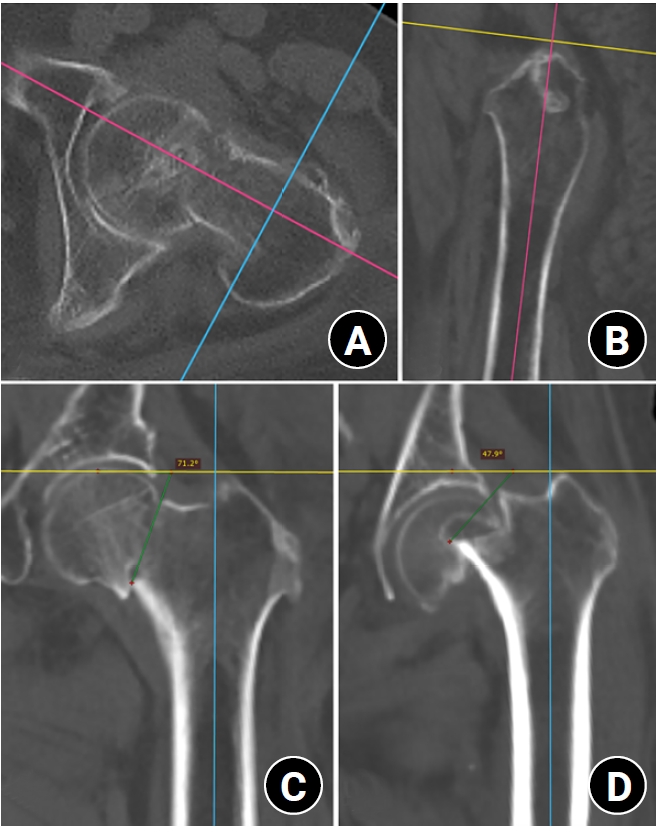

Modified Pauwels angle measurement

Modified Pauwels angle measurement using multiplanar reconstruction. (A) The head-neck axis (HNA; pink line) was identified in the axial plane using the line of the best-fit method through the center of the femoral neck isthmus. This process corrected the external rotation deformity and femoral neck anteversion. The mid-coronal plane was defined as the plane containing the HNA and oriented perpendicular to the axial plane, dividing the femoral neck into anterior and posterior regions. (B) The sagittal plane was utilized to adjust the alignment of the mid-coronal plane using the anatomical axis of the proximal femur. This adjustment corrected the lower extremity deformities and restored proper anatomical alignment. (C) The modified Pauwels angle was measured on the reconstructed mid-coronal plane as the angle between the fracture line (green line) and a line perpendicular (yellow line) to the central line of the femoral shaft (blue line). A 79-year-old female patient with a femoral neck T-score of −1.7 sustained a ground-level fall, resulting in a modified Pauwels angle of 71.2°. (D) In contrast, an 83-year-old female patient with a femoral neck T-score of −4.2 exhibited a modified Pauwels angle of 47.9° in the reconstructed mid-coronal plane.

Fig. 1. Modified Pauwels angle measurement using multiplanar reconstruction. (A) The head-neck axis (HNA; pink line) was identified in the axial plane using the line of the best-fit method through the center of the femoral neck isthmus. This process corrected the external rotation deformity and femoral neck anteversion. The mid-coronal plane was defined as the plane containing the HNA and oriented perpendicular to the axial plane, dividing the femoral neck into anterior and posterior regions. (B) The sagittal plane was utilized to adjust the alignment of the mid-coronal plane using the anatomical axis of the proximal femur. This adjustment corrected the lower extremity deformities and restored proper anatomical alignment. (C) The modified Pauwels angle was measured on the reconstructed mid-coronal plane as the angle between the fracture line (green line) and a line perpendicular (yellow line) to the central line of the femoral shaft (blue line). A 79-year-old female patient with a femoral neck T-score of −1.7 sustained a ground-level fall, resulting in a modified Pauwels angle of 71.2°. (D) In contrast, an 83-year-old female patient with a femoral neck T-score of −4.2 exhibited a modified Pauwels angle of 47.9° in the reconstructed mid-coronal plane.